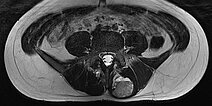

In der axialen T2-gewichteten Sequenz der MRT liegt die Läsion in der autochtonen Rückenmuskulatur. Klassischer Flüssigkeits-Flüssigkeits-Spiegel durch schwerkraftbedingte Sedimentationseffekte bei dem in Rückenlage ruhig im Gerät liegenden Patienten.